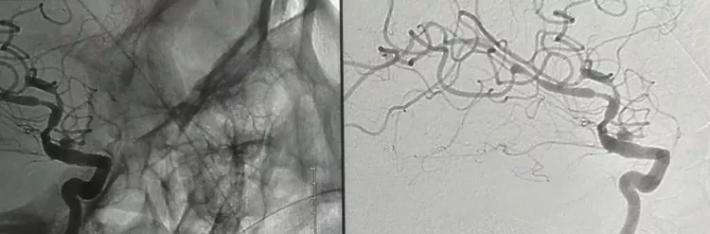

R-ICA正位:颈内动脉床突上段局部膨隆

R-ICA斜位:可见床突上段前壁一蘑菇状囊性突起,结合cT出血提示BBA,与家属沟通后选择介入治疗,我们拟采用Willis覆膜支架局部血管成形术!

释放支架后见BBA显影变浅,仅后半部分晚期显影,脉前A显影好,再次后扩。

二次后扩后颈内动脉造影见BBA逆向充盈部分显影,晚期仍有造影剂滞留,如远端再次叠套一支架必会累及脉前A,2周后复查DsA吧,希望BBA不破而且血栓自愈。

蒙片看支架释放成形很好,远端由于脉前A的原因覆盖的较短,故而有少量逆向渗漏,但是蒙片看造影剂晚期滞留明显,与家属沟通后终止手术! 2周后切线位DsA造影可看到造影剂充盈BBA,造影剂与支架间形成一充盈平面,与术后DsA形态比较明显增大,而且M1有明显的痉挛。